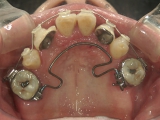

● 臼歯部の後方移動

臼歯を後方に牽引し、移動させることでスペースを確保し歯列を整えます。

抜歯矯正をした経験があり、新たに抜歯

できる歯がないため、臼歯を後方へ牽引

してスペースを確保します。

臼歯にリンガルアーチという装置を装着し、ミニインプラントを固定源に臼歯を後方に牽引します。

前突が改善し、きれいな歯並びになりました。

臼歯が後方に下がり、臼歯と小臼歯の間にスペースができました。唇側にワイヤ-をSETし、前歯の歯並びの改善を併行して行います。